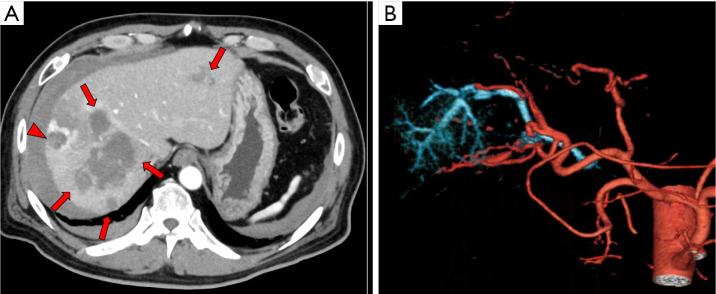

Tract hemostasis using radiofrequency ablation for hepatic arterial bleeding after percutaneous transhepatic portal embolization.